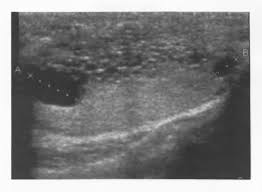

A high level of vascularity is routinely seen with neoplasia, such as teratomas. The sonographic features of this benign process must be appreciated by urologists as well so that is not mistaken for malignancy. Tubular ectasia of the rete testis (tert) is a common cause of lesions, arising as the result of epididymal obstruction or postsurgical changes to the rete testis (e.g., after a dialysis or a vasectomy). Tubular ectasia of rete testis is an acquired condition with wide spectrum of etiological factors including mechanical compression of the epididymis or spermatic cord by surgical, traumatic, neoplastic or infectious conditions and atrophic alterations in epididymal tubules due to ischemic or hormonal causes. Tubular ectasia of the rete testis (tert) is a benign entity due to dilation of the tubules of the rete testis. Its characteristic ultrasound findings have been well described in the radiologic literature. Due to the lack of vascularity, a presumptive diagnosis of tubular ectasia of the rete testis was made. Tubular ectasia of the rete testis is a benign condition that results from partial or complete obliteration of the efferent ducts. Scrotal swelling clinically was interpreted as testicular neoplasm. Recognizing this entity owing to its characteristic. Retia testes 8) represents dilated testicular mediastinal tubules. Cystic/tubular ectasia of the rete testis is a rare benign entity and must be differentiated from testicular neoplasm. It occurs due to the enlargement of the rete testis canaliculi.

Rete tubular ectasia is a disorder of the rete testis in which many benign cysts are present. This article outlines the diagnostic criteria of tert, its possible causes, its incidence and its potential evolution. The mean age at diagnosis is 60 years, and generally patients are older than 45 years. Its characteristic ultrasound findings have been well described in the radiologic literature. Tubular ectasia of the rete testis (tert) is a common cause of lesions, arising as the result of epididymal obstruction or postsurgical changes to the rete testis (e.g., after a dialysis or a vasectomy). It is a rare benign entity having a typical sonographic appearance of cluster of small anechoic structures in the confluence of the mediastinum testis. Tert is important diagnostically, because it might be confused with malignant teratoma that may likewise contain cystic areas. It is commonly associated with epididymal abnormalities (spermatocoele, epididymal cyst and epididymitis) and shares a common location with cystic dysplasia of the testis and intratesticular cysts.

Retia testes 8) represents dilated testicular mediastinal tubules. The sonographic features of this benign process must be appreciated by urologists as well so that is not mistaken for malignancy. Scrotal swelling clinically was interpreted as testicular neoplasm. Cystic/tubular ectasia of the rete testis is a rare benign entity and must be differentiated from testicular neoplasm. It is commonly associated with epididymal abnormalities (spermatocoele, epididymal cyst and epididymitis) and shares a common location with cystic dysplasia of the testis and intratesticular cysts. Tubular ectasia of the rete testis (tert) is a common cause of lesions, arising as the result of epididymal obstruction or postsurgical changes to the rete testis (e.g., after a dialysis or a vasectomy). It is usually seen in vasectomy patients presenting with scrotal discomfort, however, other causes of vas obstruction also lead to similar sonographic changes. It is a rare benign entity having a typical sonographic appearance of cluster of small anechoic structures in the confluence of the mediastinum testis. Tubular ectasia of rete testis is an acquired condition with wide spectrum of etiological factors including mechanical compression of the epididymis or spermatic cord by surgical, traumatic, neoplastic or infectious conditions and atrophic alterations in epididymal tubules due to ischemic or hormonal causes. Rete tubular ectasia is a disorder of the rete testis in which many benign cysts are present. Tubular ectasia of the rete testis is a benign condition that results from partial or complete obliteration of the efferent ducts. It is most commonly discovered by ultrasound that is performed to evaluate a mass, swelling, or pain, as in our case. The mean age at diagnosis is 60 years, and generally patients are older than 45 years.